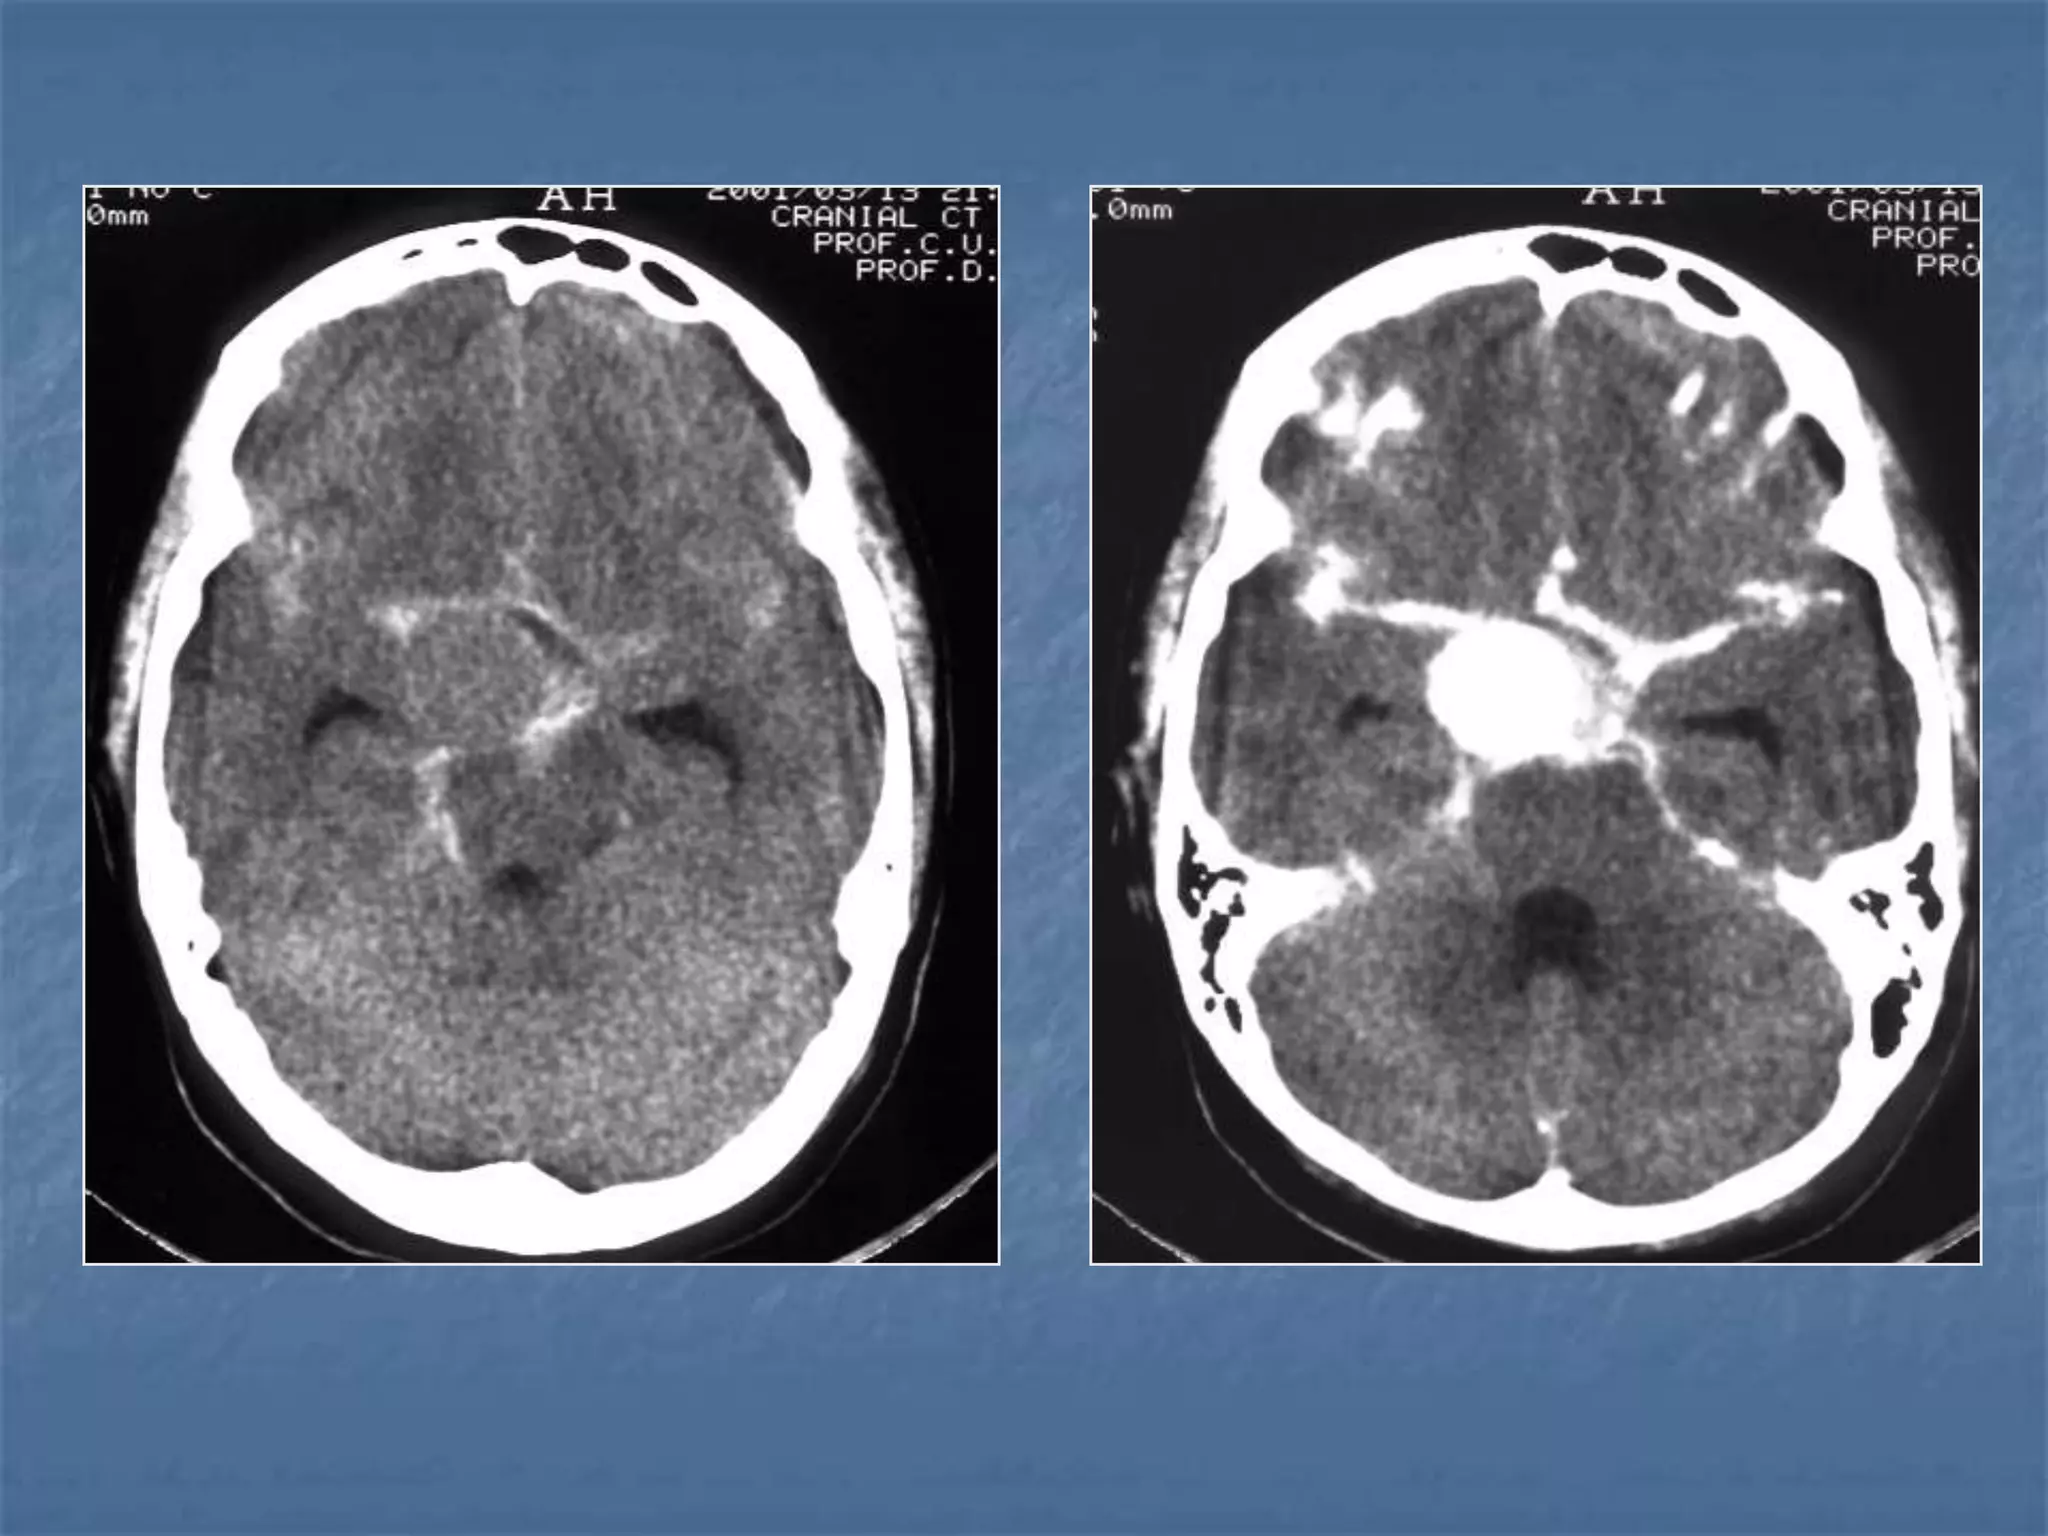

Subarachnoid hemorrhage

 In the absence of trauma, the most common cause

of subarachnoid hemorrhage is a ruptured cerebral

aneurysm. Cerebral aneurysms tend to occur at

branch points of intracranial vessels and thus are

frequently located around the Circle of Willis.

Common aneurysm locations include the anterior

and posterior communicating arteries, the middle

cerebral artery bifurcation and the tip of the basilar

artery. Subarachnoid hemorrhage typically presents

as the "worst headache of life" for the patient.

Detection of a subarachnoid hemorrhage is crucial

because the rehemorrhage rate of ruptured

aneurysms is high and rehemorrhage is often fatal.

 CT is currently the imaging modality of choice because

of its high sensitivity for the detection of subarachnoid

hemorrhage. CT is most sensitive for acute

subarachnoid hemorrhage. After a period of days to

weeks CT becomes much less sensitive as blood is

resorbed from the CSF. If there is a strong clinical

indication, LP may be warranted despite a negative CT

since small bleeds can be unapparent on imaging.

On CT, a subarachnoid hemorrhage appears as high

density within sulci and cisterns. The insular regions

and basilar cisterns should be carefully scrutinized for

subtle signs of subarachnoid hemorrhage.

Subarachnoid hemorrhage may have associated

intraventricular hemorrhage and hydrocephalus.